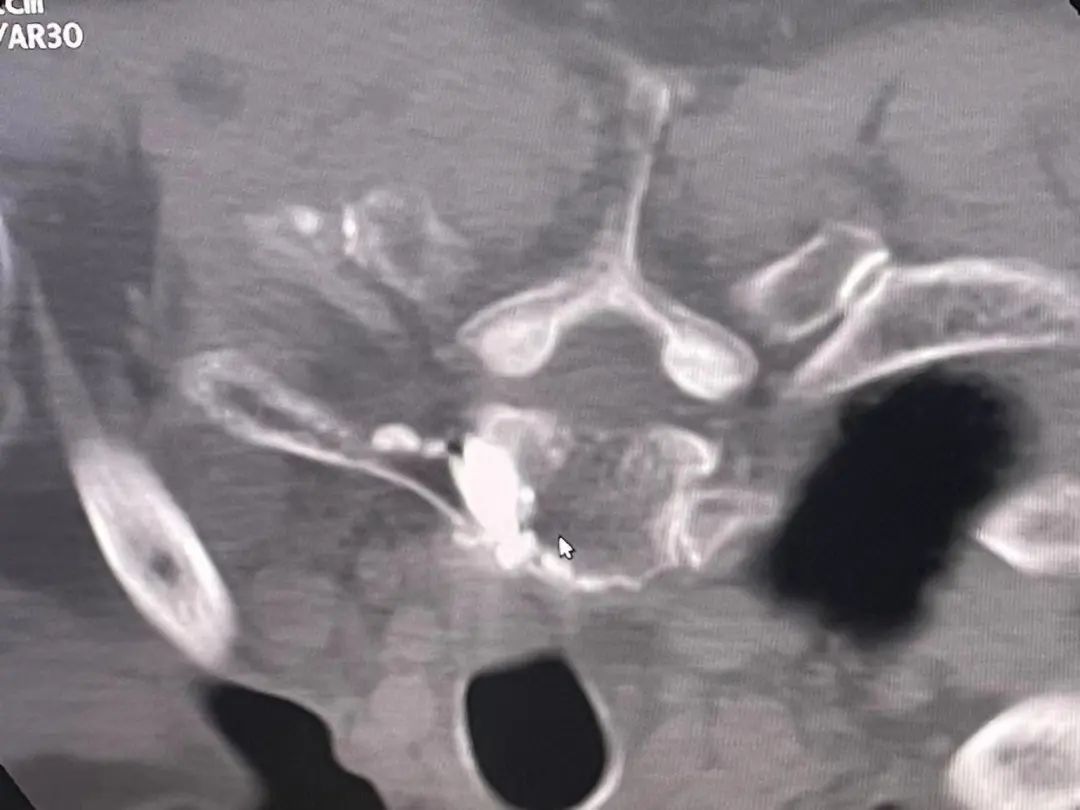

近日,我院骨科团队在CT引导下成功完成一例高位胸椎(TI)转移瘤骨水泥填充成形术。高位胸椎椎体成形手术定位难、手术操作难度和风险较大。在CT定位引导下,可以准确定位肿瘤病灶,设计精确穿刺路线,对肿瘤病灶精准治疗提供了保障。

经皮椎体成形术(percutaneous vertebroplasty,PVP),临床主要被用于治疗骨质疏松性骨折和疼痛性椎体血管瘤的治疗。PVP技术被用于脊柱转移瘤治疗的原理是,通过骨穿刺针经皮穿刺入椎体后,在病变椎体内注射骨水泥。骨水泥在椎体内会逐渐变硬。在骨水泥变成固体的过程中骨水泥的温度会升高并释放热量,使肿瘤组织及病灶周围神经末梢坏死。通过骨水泥填充,支撑被肿瘤破坏的椎体结构,防止椎体进一步塌陷,并缓解疼痛。